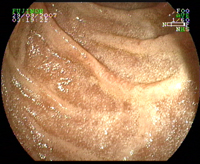

Duodénum normal